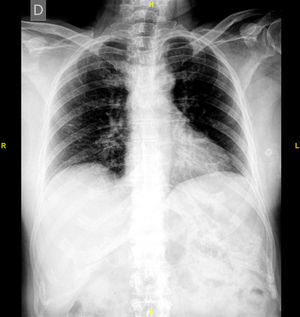

The study of the extension of the disease included BS, which revealed the presence of a diffuse blastic lesion in the sternal manubrium, suggestive of Paget's disease or a metastatic lesion (Fig. 1). The study was completed with radiographs of chest, lumbosacral spine and pelvis (Figs. 2 and 3), in which the only finding was increased density in L4-L5 facet joints. Chest CT, recommended by the professionals in nuclear medicine, revealed sclerosis in the sternal manubrium, suggestive of metastasis (Fig. 4).